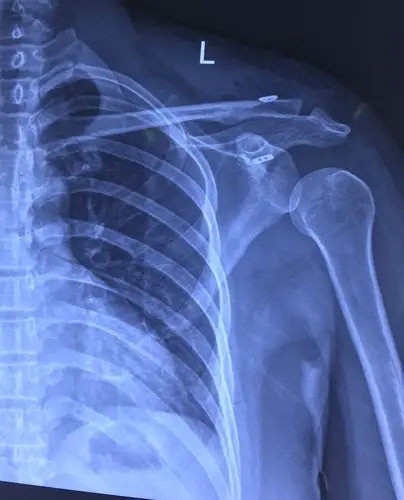

肩锁关节脱位关节镜微创复位固定